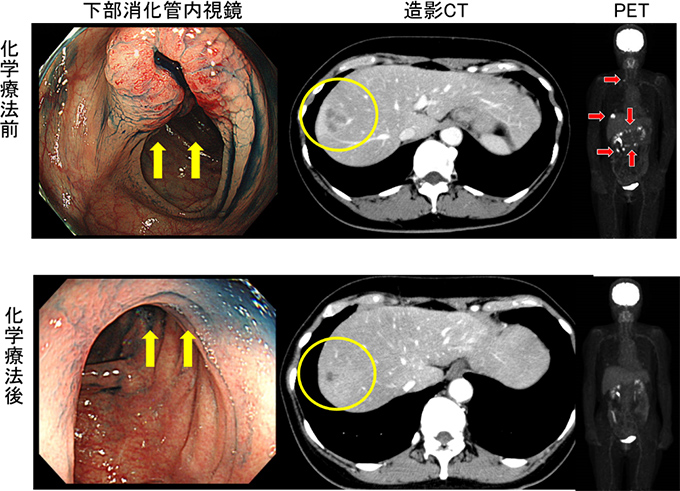

56歳女性。横行結腸癌同時性肝転移(肝S8)+傍大動脈リンパ節転移を認め当センターへ紹介となりました。B-mab+XELOX 3コース施行で著効を示し、PETでもnear CR(図1)となりました。腹腔鏡下肝部分切除術+右半結腸切除術を施行しました(図2−4)。手術時間は8時間25分、出血量は50g。術後14日目で退院となりました。原発巣、肝転移巣ともに病理学的CRでした。

図1 化学療法前後の画像評価:下部消化管内視鏡・造影CT・PET、それぞれの画像